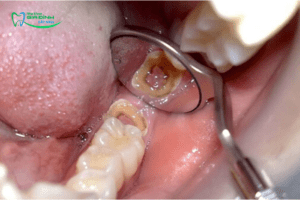

Răng khôn bị sâu

Do vị trí nằm sâu trong cùng của hàm, răng khôn rất khó được làm sạch kỹ lưỡng. Thức ăn và mảng bám dễ tích tụ, tạo điều kiện cho vi khuẩn phát triển và gây sâu răng. Khi răng khôn bị sâu, người bệnh thường cảm thấy đau nhức kéo dài, ê buốt khi ăn uống, đặc biệt là với thức ăn nóng hoặc lạnh. Nếu không điều trị sớm, tình trạng này có thể tiến triển thành viêm tủy, nhiễm trùng và gây đau dữ dội hơn.